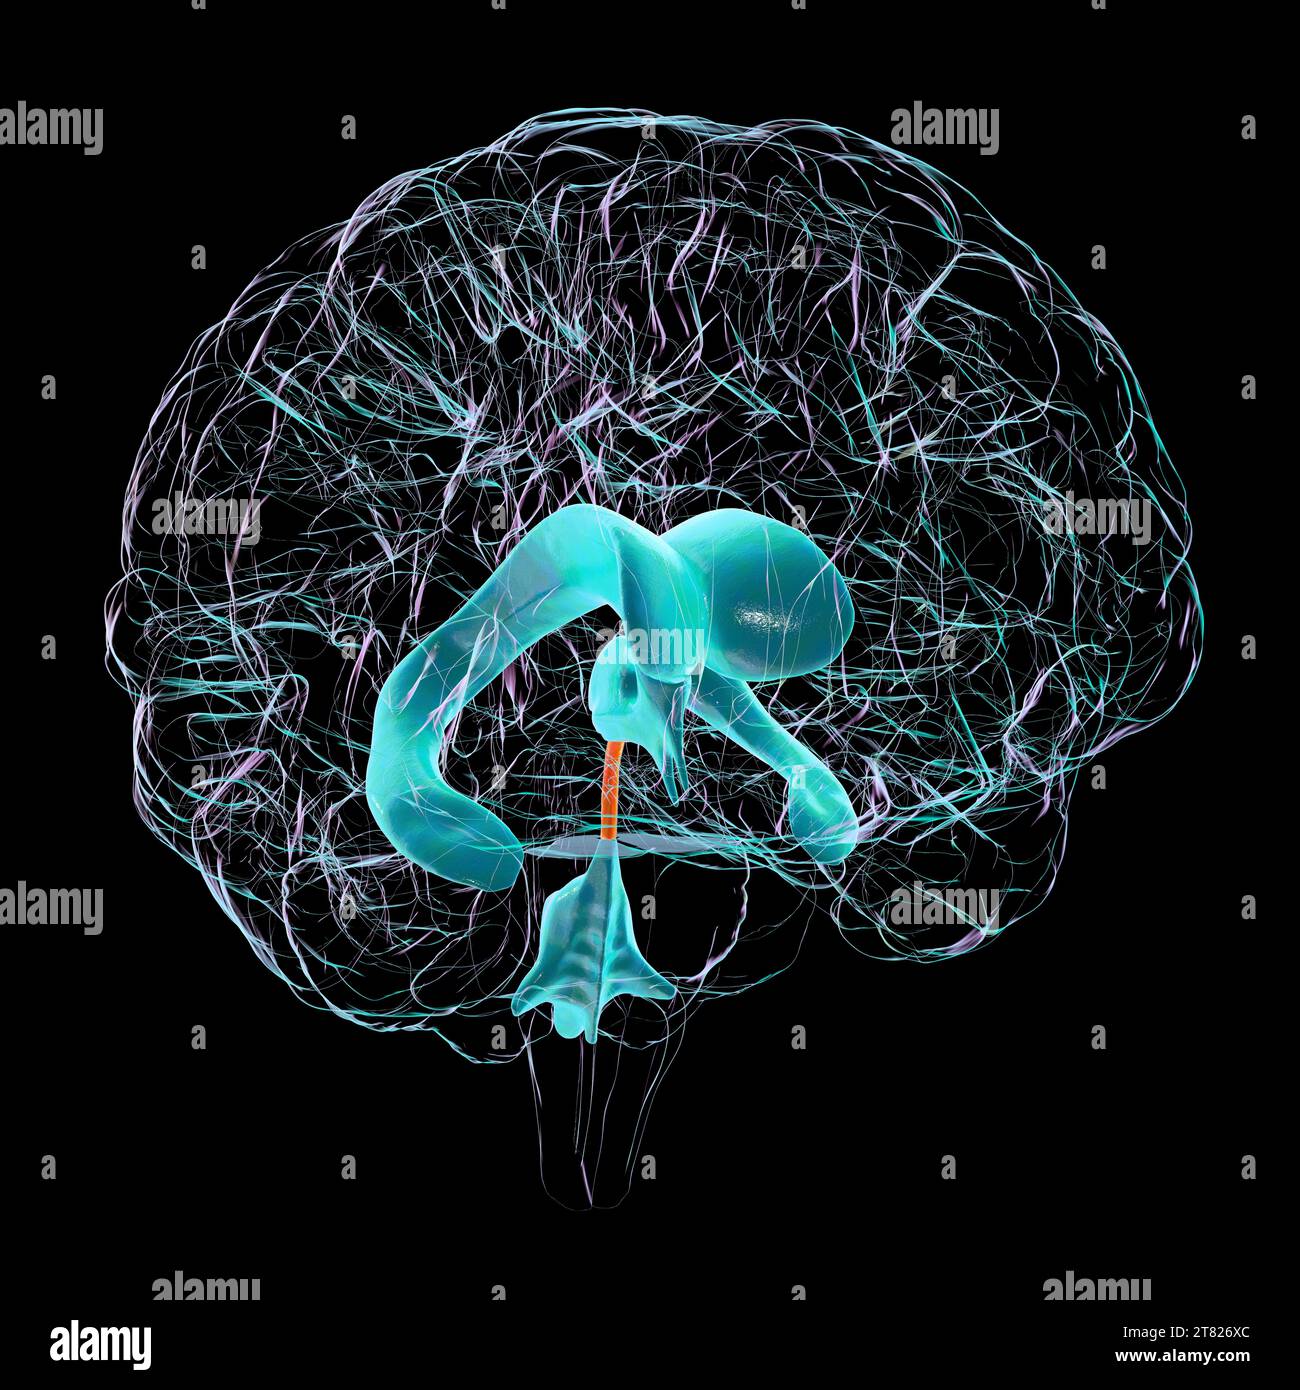

RF2T7NGWH–Ventrikel und zerebrales Aquädukt laterale Röntgenansicht 3D-Rendering-Illustration. Menschliches Gehirn und Ventrikelsystem Anatomie, Medizin, Gesundheitswesen, Scienc

RF2T7NGWK–Ventrikel und zerebraler Aquädukt lateral in Farben Röntgenbild-3D-Rendering-Illustration. Menschliches Gehirn und Ventrikelsystem Anatomie, medizinisch, gesund

RF2T7NGWR–Ventrikel und Hirn-Aquädukt-Röntgenprofil Nahansicht 3D-Rendering-Illustration mit Körperkonturen. Anatomie des menschlichen Gehirns und des Ventrikelsystems,

RF2T7NGWW–Ventrikel und zerebraler Aquädukt in Farben Röntgenprofil Nahansicht 3D-Rendering-Illustration. Anatomie des menschlichen Gehirns und des Ventrikelsystems, medizinisch,

RF2T030GG–Röntgenlaterale Darstellung der Hirnventrikel 3D-Darstellung mit Körperkonturen. Anatomie des menschlichen und ventrikulären Systems, Medizin, Biologie, Scienc

RF3C7H8A6–Abbildung des Gehirns mit hervorgehobenem Aquädukt (rot) und ventrikulärem System (blau), Darstellung des Liquorflusses.

RF3C7H8AA–Abbildung des Gehirns mit hervorgehobenem Aquädukt (rot) und ventrikulärem System (blau), Darstellung des Liquorflusses.

RF3C7H8AF–Abbildung des Gehirns mit hervorgehobenem Aquädukt (rot) und ventrikulärem System (blau), Darstellung des Liquorflusses.

RF3C7H8A3–Abbildung des Gehirns mit hervorgehobenem Aquädukt (rot) und ventrikulärem System (blau), Darstellung des Liquorflusses.